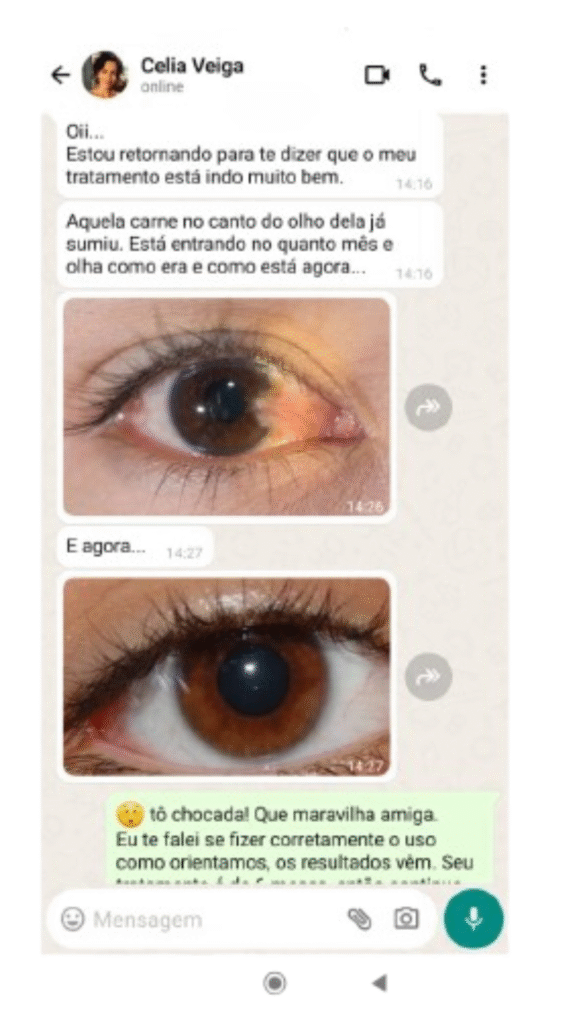

Mais de 100 mil pessoas já recuperaram sua visão com Vision Gold Premium!

Veja o que dizem alguns de nossos clientes satisfeitos:

Os efeitos do tratamento com Vision Gold podem ser percebidos em um prazo relativamente curto. De acordo com a experiência de nossos clientes, geralmente entre 10 e 20 dias já é possível notar uma melhora significativa na saúde ocular. Vision Gold é um produto 100% natural, desenvolvido para proporcionar benefícios visíveis de maneira segura e eficaz. Lembre-se de seguir as instruções de uso corretamente para obter os melhores resultados.